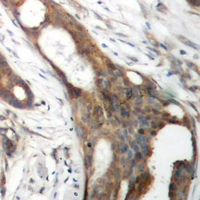

IHC (Immunohiostchemistry)

(Immunohistochemical analysis of ASCT1 staining in human ovarian cancer formalin fixed paraffin embedded tissue section. The section was pre-treated using heat mediated antigen retrieval with sodium citrate buffer (pH 6.0). The section was then incubated with the antibody at room temperature and detected using an HRP conjugated compact polymer system. DAB was used as the chromogen. The section was then counterstained with haematoxylin and mounted with DPX.)